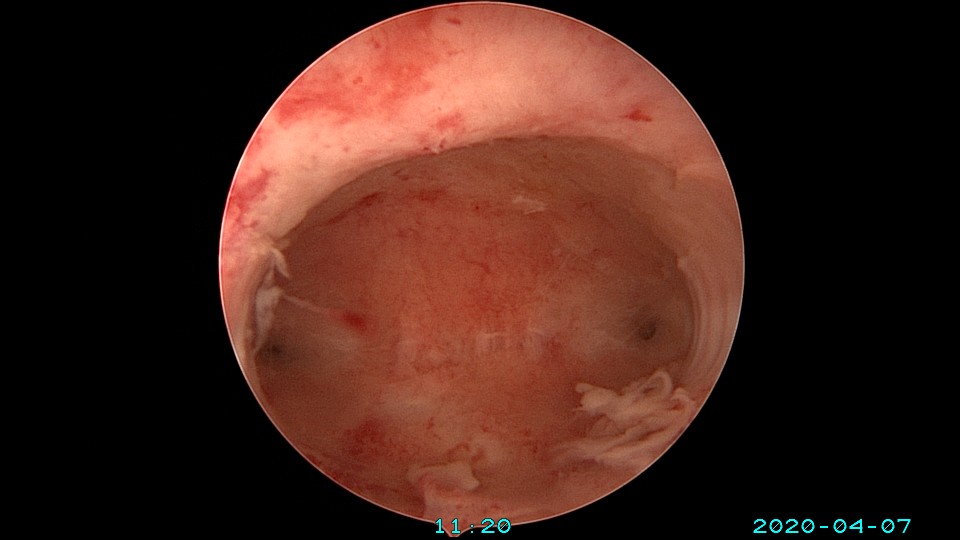

患者36岁,G3P0,自然流产3次,发现宫腔粘连3个月。2020年3月宫腔镜探查,子宫前倾后屈位,宫深8.5cm,宫颈管粘连狭窄,扩宫进入宫腔,见宫腔中下段两侧壁粘连,剪刀及双极电切分粘,宫腔形态恢复正常,双侧输卵管开口显露。2020年4月宫腔镜二探取球囊,宫腔形态正常,双侧输卵管开口可见。2021年6月自然妊娠,2022年2月足月剖宫产分娩。现42岁,G4P1。